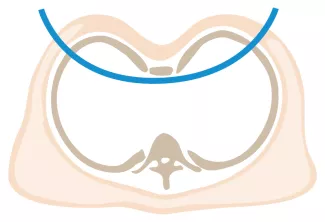

Preoperatively, your insurance carrier may require a CT scan to measure the Pectus Severity Index (PSI, also known as the Haller Index), which is the the ratio of the width of the chest wall to the depth at the deepest point of the deformity. This value usually must exceed 3.2 to be considered severe enough to be surgically corrected.